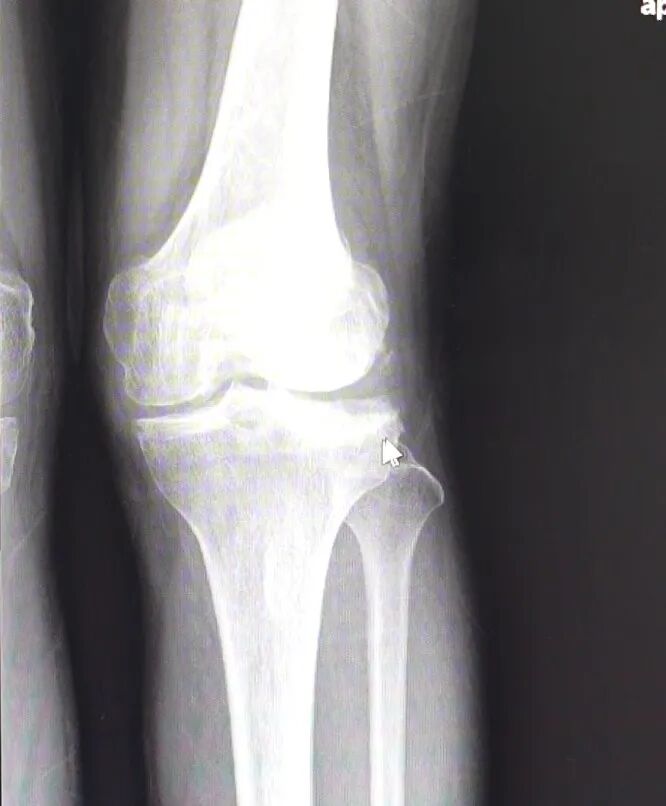

△手术前

医生在检查患者后,发现患者是很严重的类风湿性关节炎,膝关节出现外翻畸形,已达中重度,需要手术治疗。

而对于存在骨骼畸形的患者,传统手术操作存在一些困难。“以往这种手术特别依赖医生的经验,所以也会出现一些误差,导致手术效果不佳。”常州一院骨关节科主任医师王益民表示。